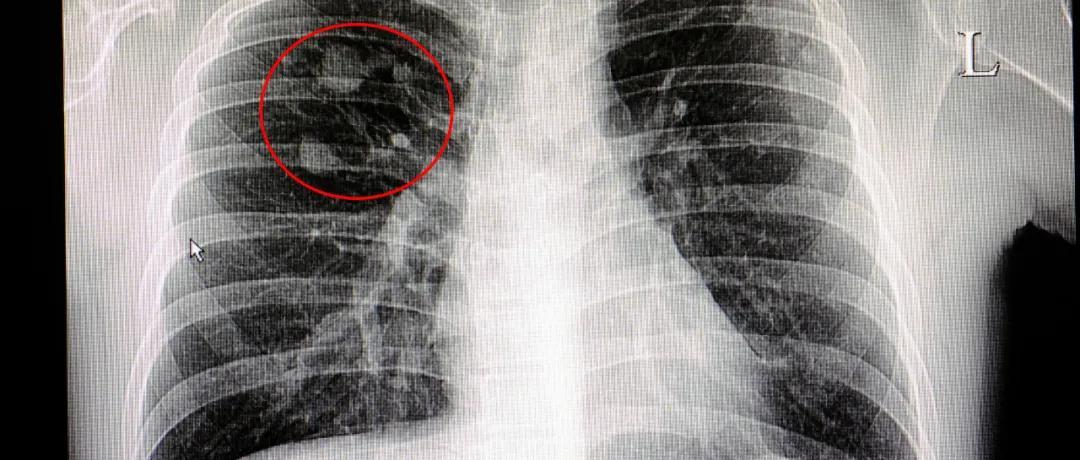

肺結節指直徑在3釐米以下的局竈性、類圓形、密度增高的實性或亞實性肺部陰影。很多人體內都有一些小的肺結節,目前體檢發現肺結節的幾率達10%~30%。

數據顯示,在重度吸菸人羣中,6毫米以上肺結節的惡性概率約爲4%;不吸菸人羣中,5毫米以下肺結節的惡性概率極低。

從結節大小來看,直徑在1釐米以下的,尤其是小於5毫米的微小結節,情況不嚴重者一般無需處理,有惡變風險者密切觀察。

普通健康人羣

• 5毫米以下的結節定期觀察,無需干預;

• 5毫米~1釐米,尤其是8毫米以上的結節,按照3個月、6個月、12個月的週期規律複查。

重度吸菸等高危人羣

• 8毫米以上的結節應引起警惕;

• 1釐米以上的結節需密切複查,如不能排除惡性,建議積極進行活檢或手術治療;疑似炎症的結節,遵醫囑短期服用抗生素觀察即可。

2024年,四川大學華西醫院呼吸與危重症醫學科主任醫師李爲民教授團隊在英國《自然醫學》雜誌發表最新研究成果,以中國人羣數據爲基礎,對肺結節惡性風險進行了精準分級和個性化管理,大家可以參考: